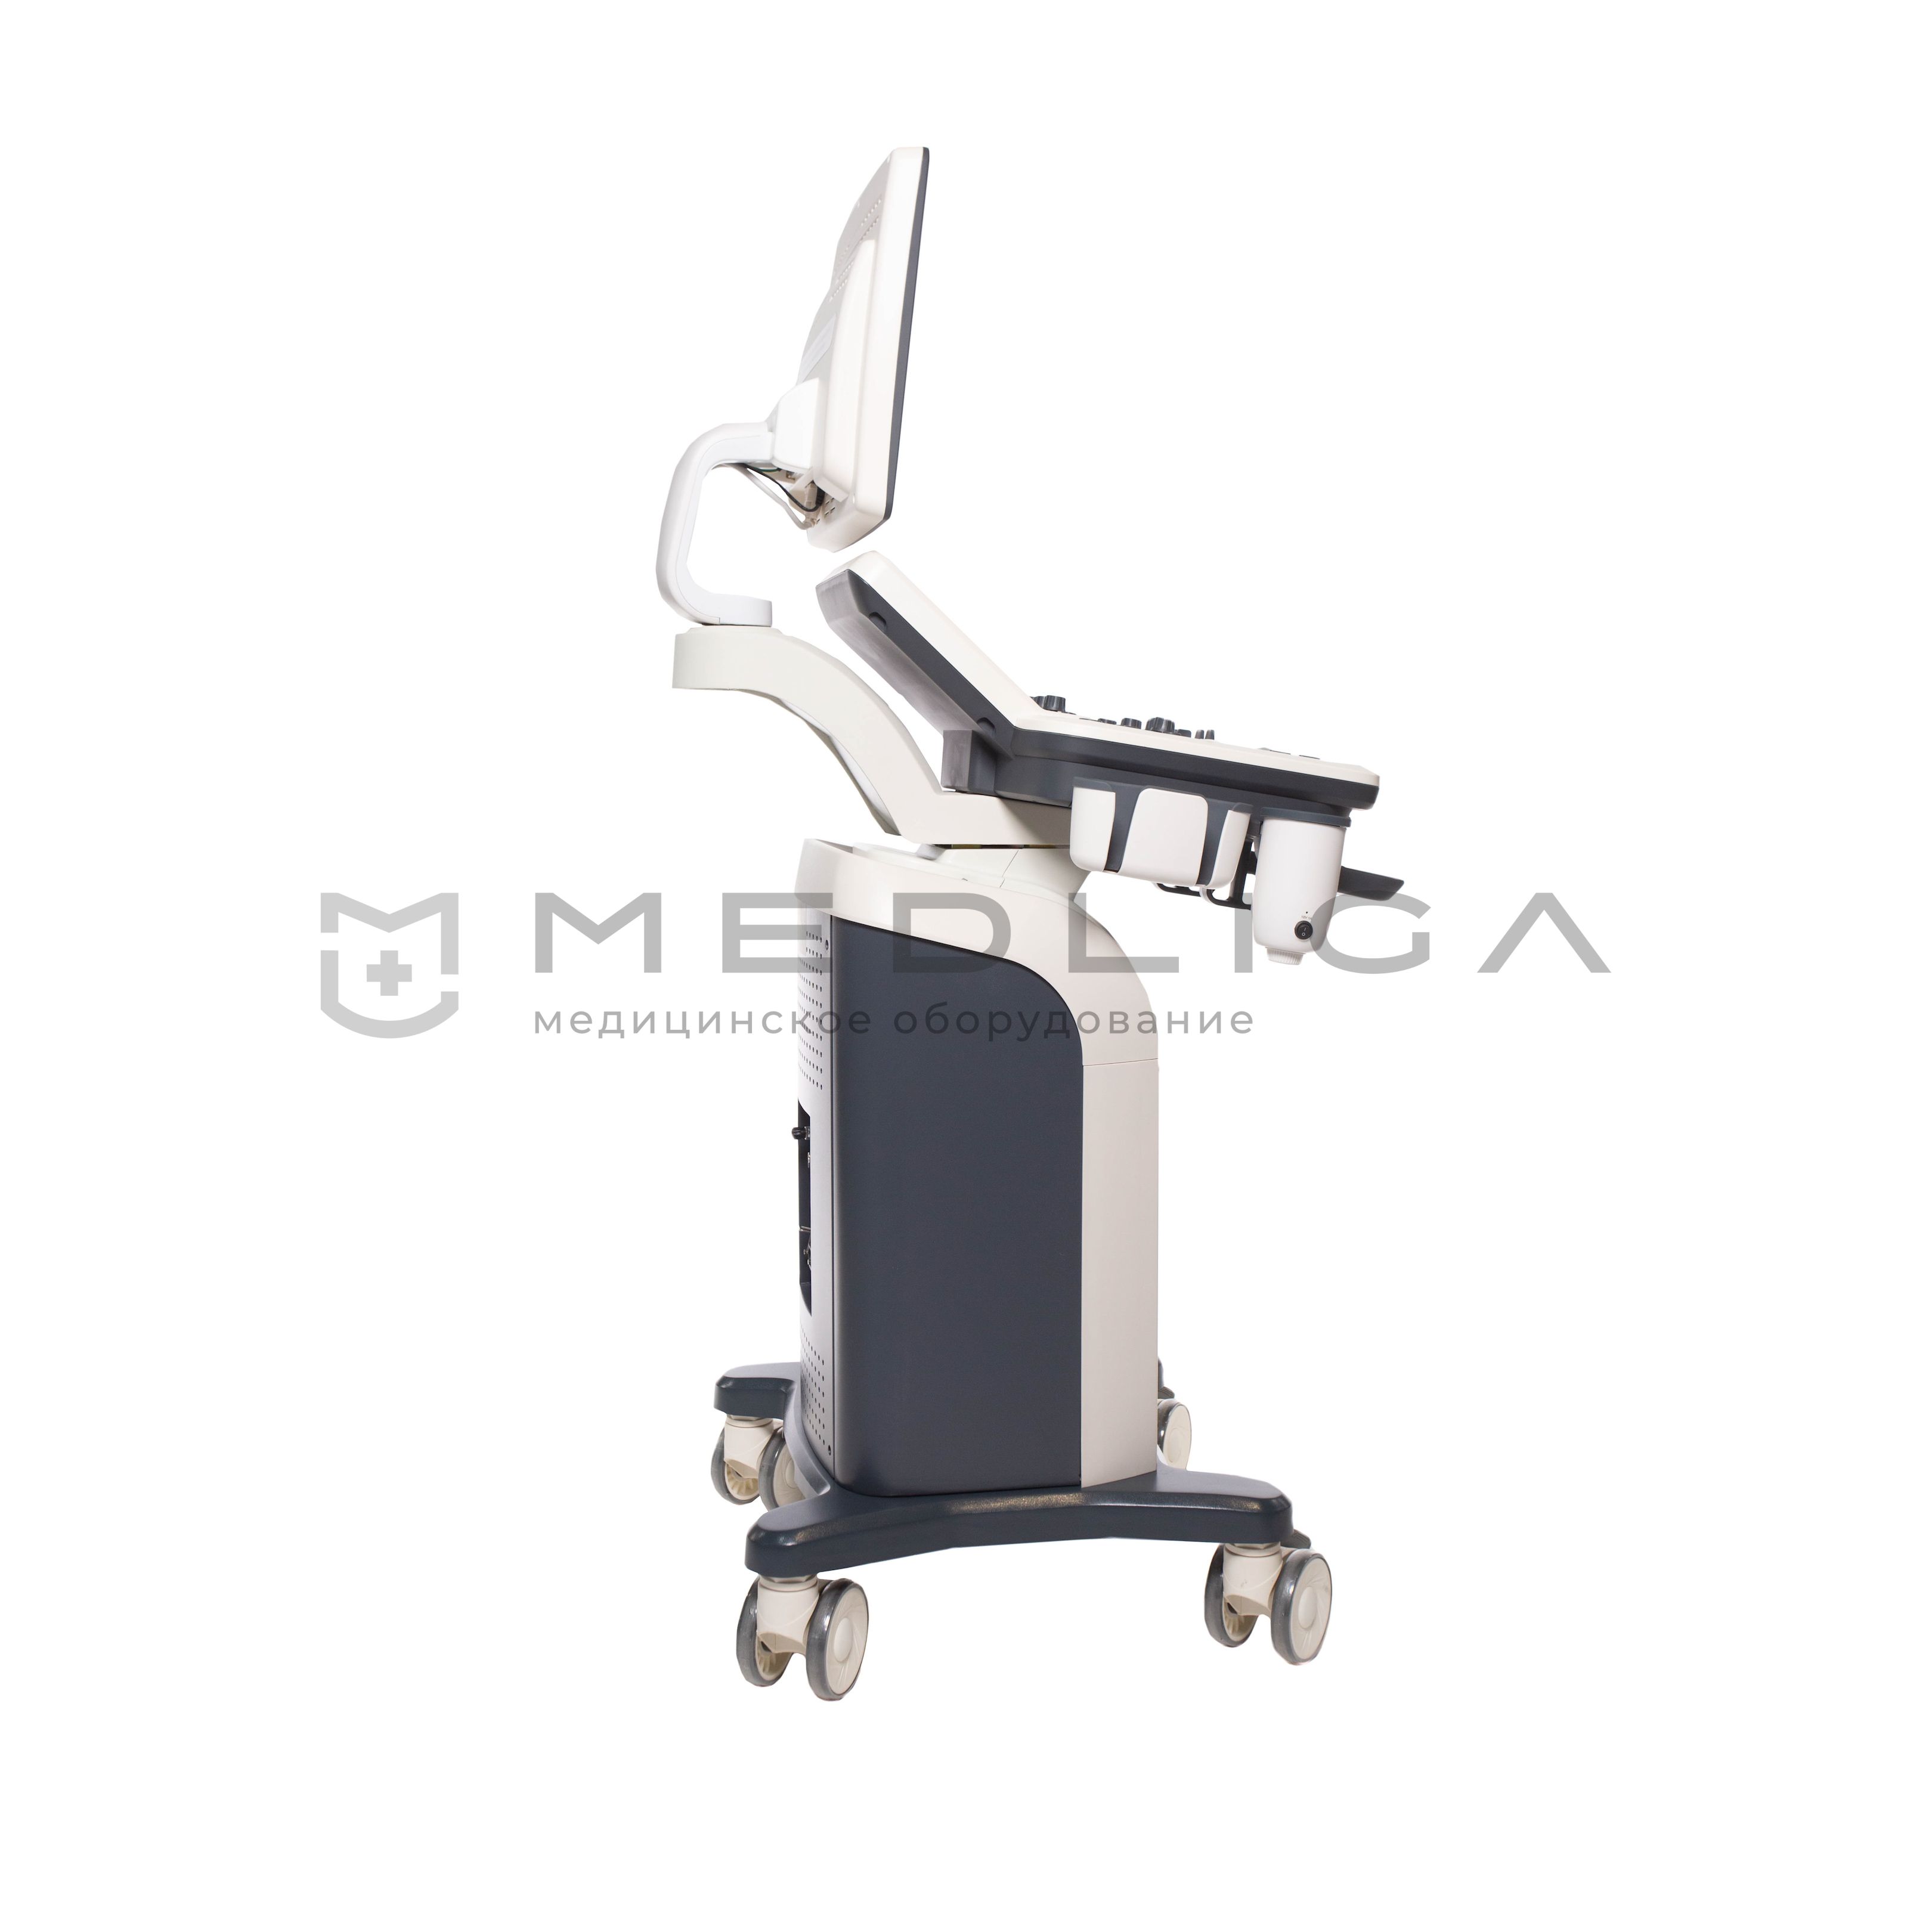

Ветеринарный УЗИ-сканер VETLIGA SP7

VETLIGA SP7 – ветеринарный ультразвуковой аппарат, работающий на новейшей технологической платформе uSeed. Прибор отличается эффективной обработкой и визуализацией изображений экспертного уровня, высокой производительностью и пропускной способностью.

VETLIGA SP7 - ветеринарный ультразвуковой аппарат, работающий на новейшей технологической платформе uSeed. Прибор отличается эффективной обработкой и визуализацией изображений экспертного уровня, высокой производительностью и пропускной способностью за счет предустановленных автоматических программ для исследования животных. 4 активных порта дают возможность подключать необходимые датчики и проводить весь спектр диагностических мероприятий.

Портативные сканеры легкие (5-15 кг) и компактные (размером с ноутбук), активно применяются в ситуациях, требующих скорой медицинской помощи, как на выездах, так и внутри лечебного учреждения. В больнице переносные приборы часто устанавливаются на специальную тележку, оснащенную держателями датчиков и другими опциями.

Стационарные аппараты также называют передвижными. Работают от электросети. Обеспечивают высокую производительность, обеспечивают точную диагностику, имеют дисплей с большей диагональю и наиболее удобную панель управления. Также могут иметь встроенную аккумуляторную батарею.